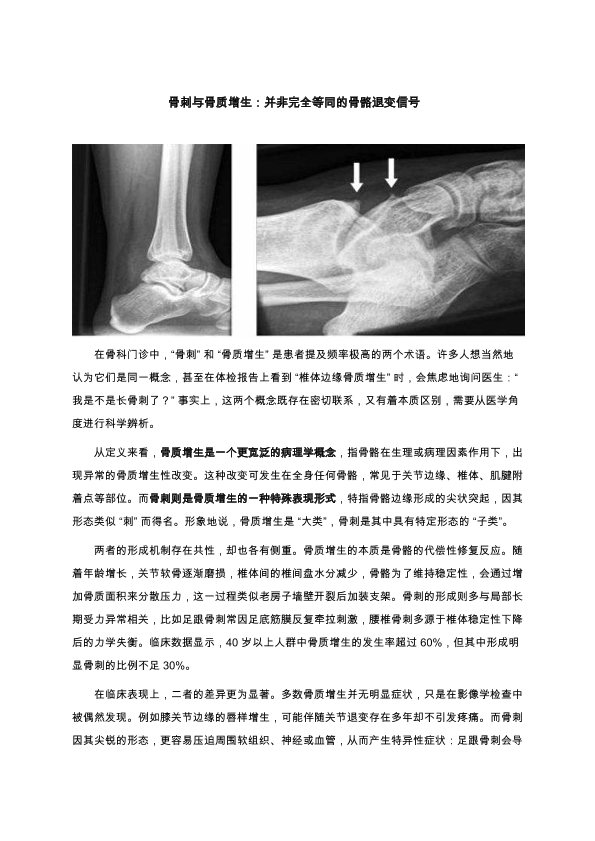

骨刺与骨质增生:并非等同的骨骼退变信号